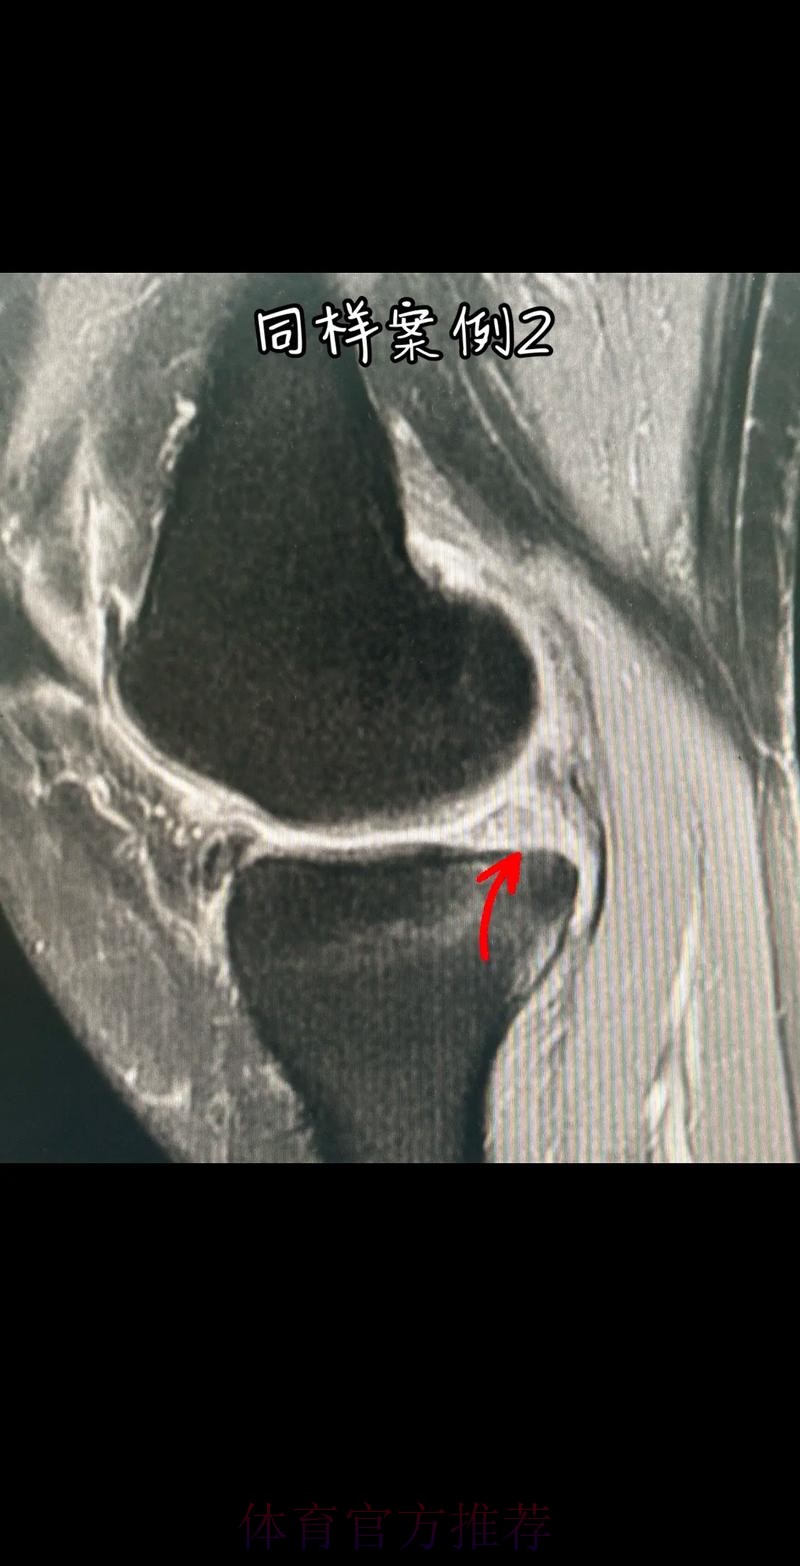

从医学角度看 半月板是膝关节内一块呈“C”形的软骨结构 其作用是缓冲冲击 稳定膝关节 并帮助分散压力 “左膝内侧半月板撕裂”通常说明在一次急停 旋转 或对抗中 半月板受到了超过其承受极限的力导致结构损伤 这类伤病常见于足球 篮球等需要频繁变向和对抗的项目 对于职业球员而言 半月板损伤严重程度不一 但共同点是都会影响支撑发力 跳跃以及变向时的稳定性 而官方给出的“预计伤缺6-8周”这个时间区间 往往对应的是中度损伤或通过微创手术加积极康复能够较快回归的情况 也意味着暂时没有出现必须长时间休战的最坏结果